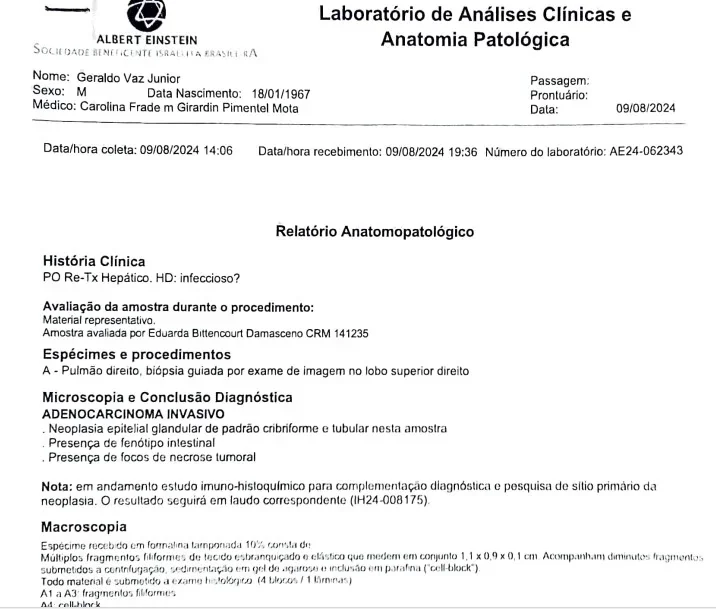

Geraldo Vaz Junior, de 58 anos, passou por um transplante de fígado em março de 2023, acreditando que seria o início de uma nova fase após enfrentar a hepatite C. No entanto, meses depois, exames revelaram que o órgão transplantado continha um adenocarcinoma, um tipo de tumor maligno. Pouco tempo depois, ele foi diagnosticado com metástase pulmonar do mesmo câncer.

Desde então, Geraldo precisou realizar um novo transplante e passou a fazer sessões de quimioterapia. Ao lado do marido, Márcia Helena Vaz, sua esposa, iniciou uma mobilização nas redes sociais e nas ruas de São Paulo para cobrar esclarecimentos das autoridades. Ela afirma que o silêncio institucional pode permitir a repetição de erros semelhantes.